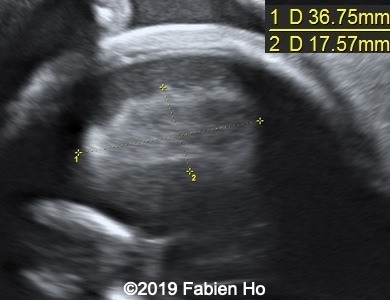

Our US examination at 27 weeks of pregnancy revealed the following anomalies, and then we decided to performed a fetal brain MRI at 28 weeks of pregnancy.

Images 1-3: in the left frontal lobe, hyperechoic with hypoechoic center lesion within the deep and periventricular white matter. Interestingly, this lesion has no mass effect on the lateral ventricle, and it has smooth margins.